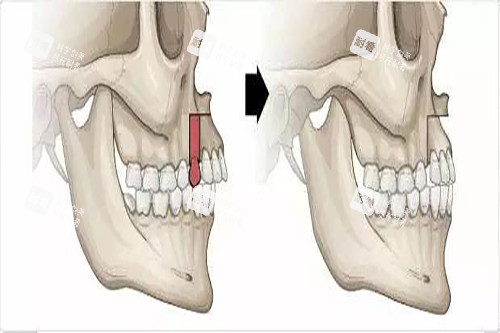

万启龙的“正畸-正颌联合治疗”,核心就俩字:“配合”。术前正畸先通过牙套调整牙齿位置,把“歪七扭八”的牙排整齐,消除牙齿的“代偿性倾斜”(比如地包天患者为了咬合,下牙会故意往前长);术中正颌再精细切割、移动颌骨,把“错位的骨头”摆回正位;术后正畸然后“微调”,让牙齿和骨头理想贴合,咬合稳如“齿轮”。

28岁的小王是典型的“凸嘴+下巴后缩”,侧面看像“月亮脸”,拍照必须抿嘴,否则像在“生气”。万启龙给她的方案是:术前正畸1年,用隐形牙套把上牙往回收、下牙往前拉;术中采用“上颌LeFortⅠ型截骨+下颌矢状劈开术”,把上颌骨往后推3毫米,下颌骨往前移5毫米;术后正畸3个月,调整牙齿咬合。

万启龙的方案更“狠”:术前正畸1年半,用固定矫治器把上牙“拉”出来、下牙“压”回去;术中采用“上颌LeFortⅠ型截骨+下颌矢状劈开术+颏成形术”,把上颌骨往前推5毫米,下颌骨往后退7毫米,同时调整下巴形态;术后正畸6个月,精细调整咬合。